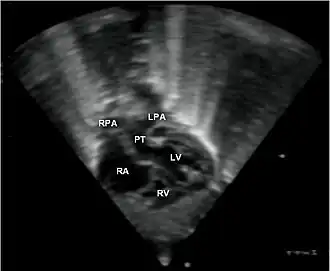

Echocardiogram van transpositie van de grote vaten | ||||

Transpositie van de grote vaten (in het Engels: transposition of the great arteries/TGA) is een aangeboren hartafwijking waarbij de aorta en de longslagader zijn omgewisseld.